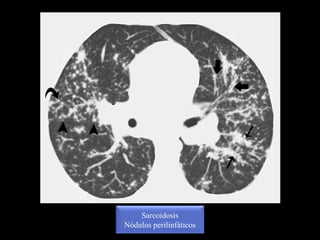

Nodulos perilinfáticos

Sarcoidosis

Nódulos perilinfáticos